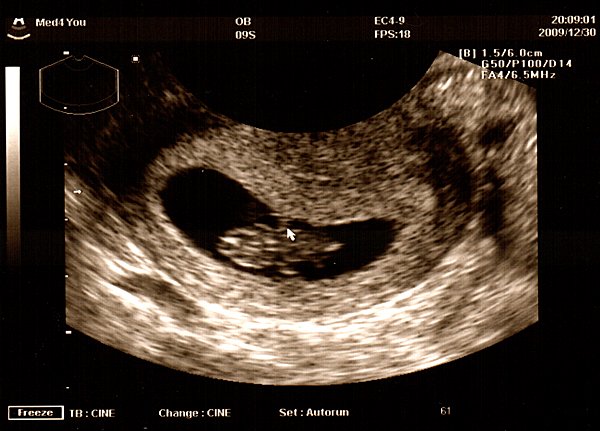

Pocakfotók nagyon szépek, és az UH-os felvételek is izgalmasak.